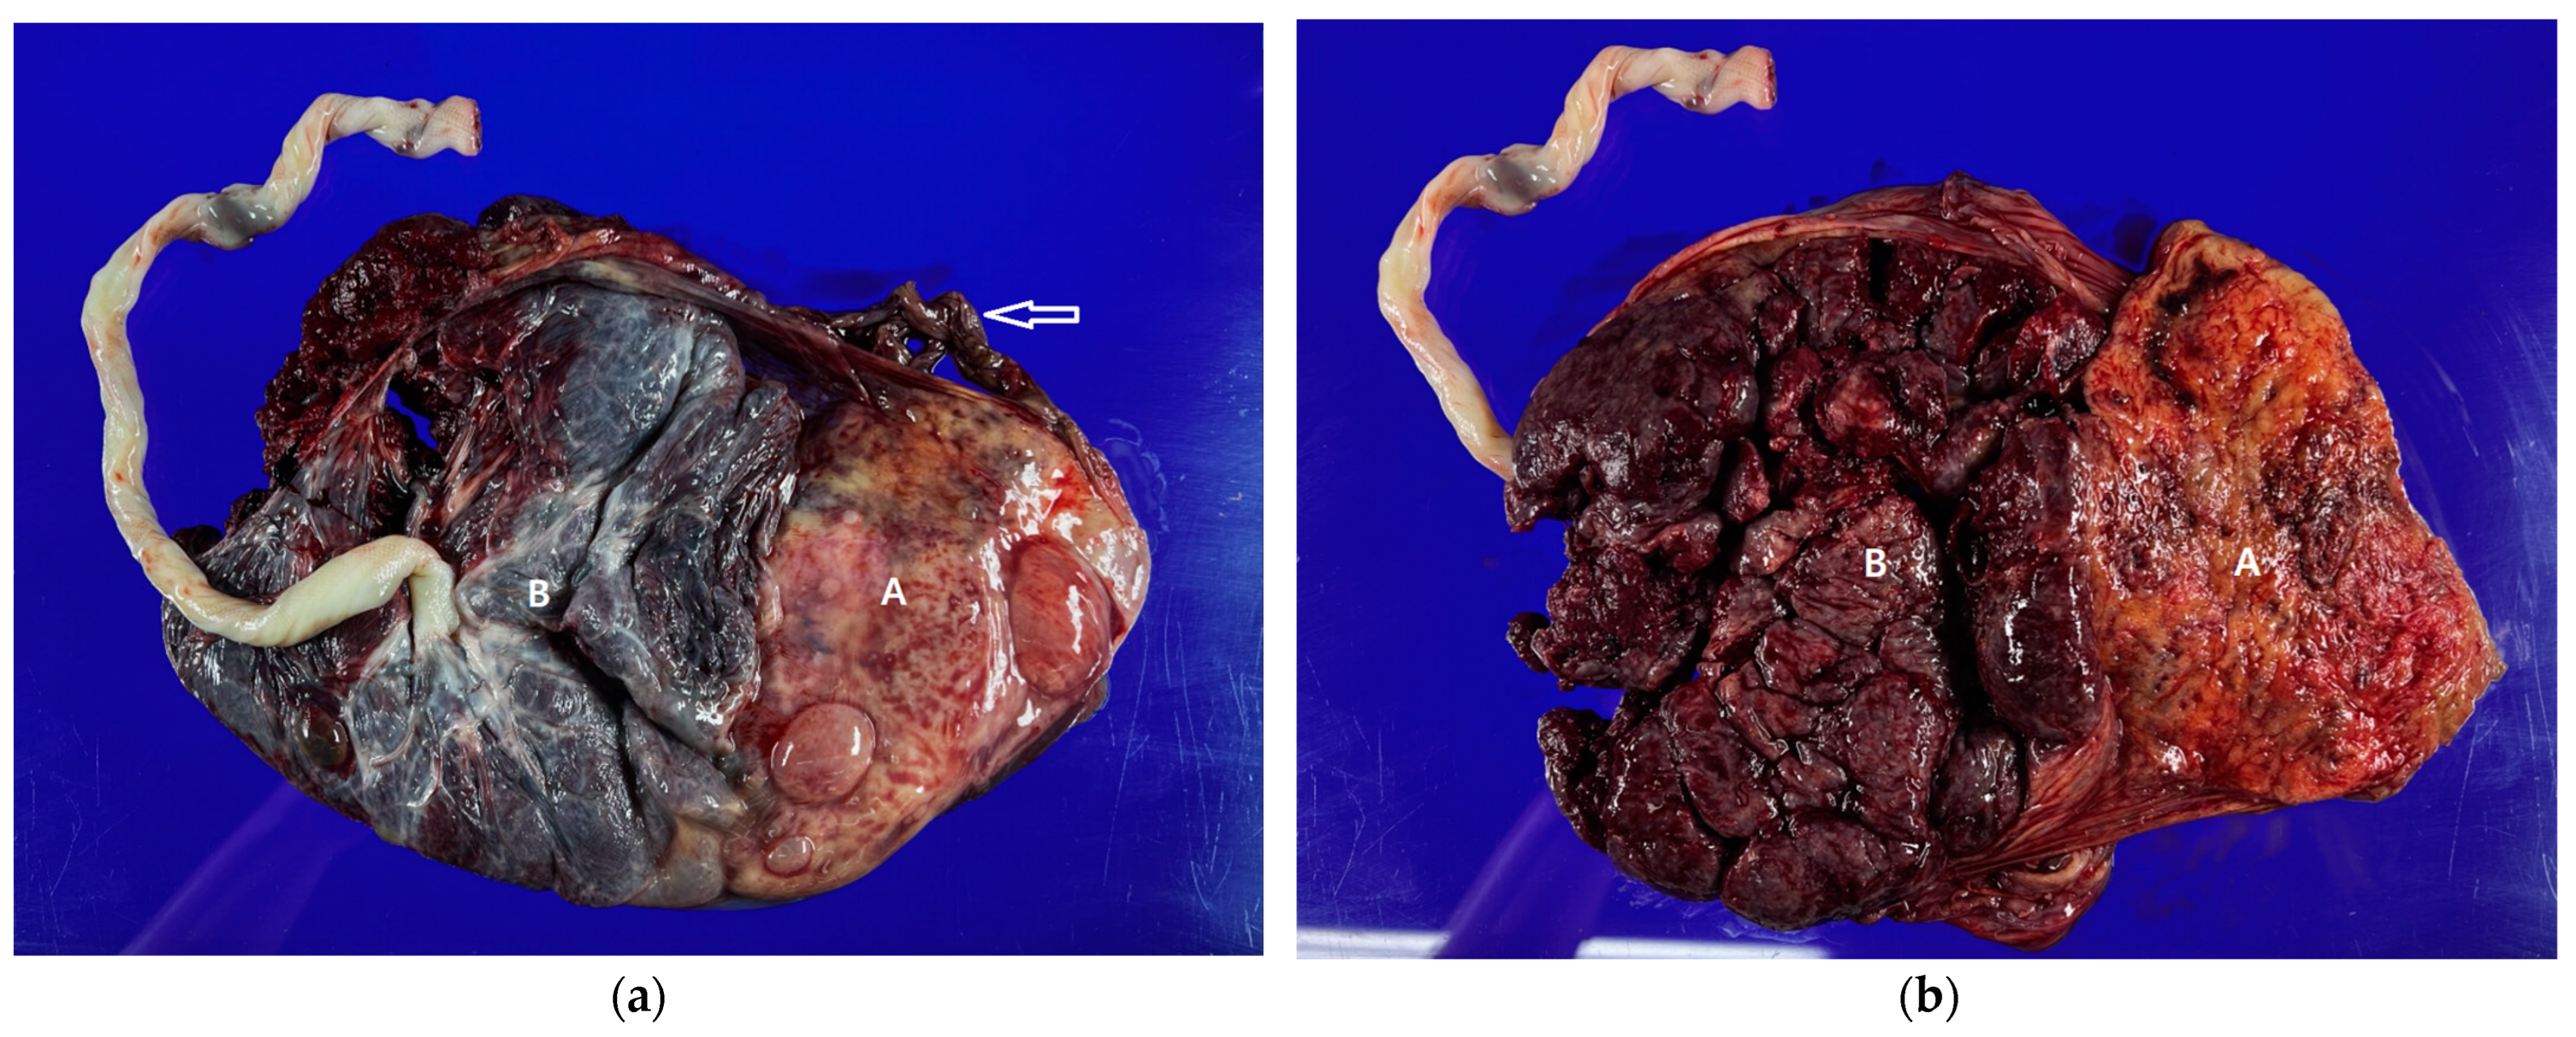

2. Case Report